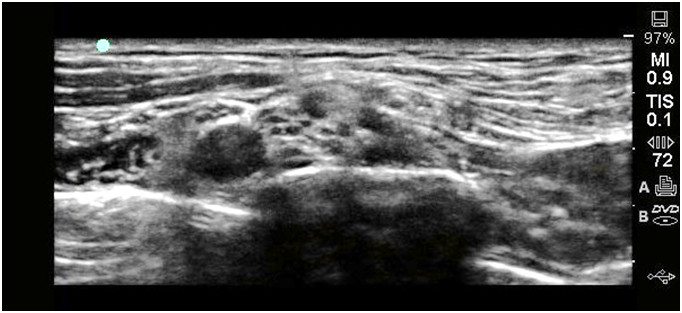

U 52-letniego mężczyzny z otyłością (BMI 44 kg/m2), zespołem hipowentylacji otyłych (terapia CPAP) wykonano blokadę splotu ramiennego z dostępu zaprezentowanego na załączonym obrazie sonoanatomicznym do zabiegu repozycji i stabilizacji złamania nasady bliższej kości ramiennej. W trakcie zabiegu doszło do dekompensacji oddechowej wymagającej natychmiastowej instrumentacji dróg oddechowych oraz przedłużonej wentylacji w okresie pooperacyjnym. Wskaż najbardziej prawdopodobną przyczynę zaistniałej sytuacji: